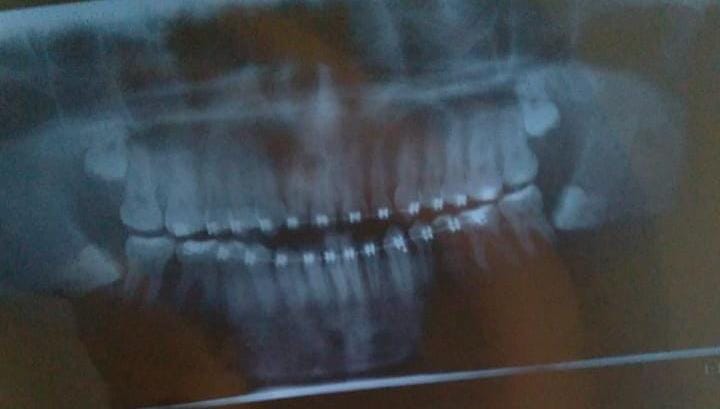

I would like to know this because it looks like my wisdom tooth is going to be impacted. Would that affect the appearance a lot?

And will my wisdom tooth grow properly? an x-ray below to see